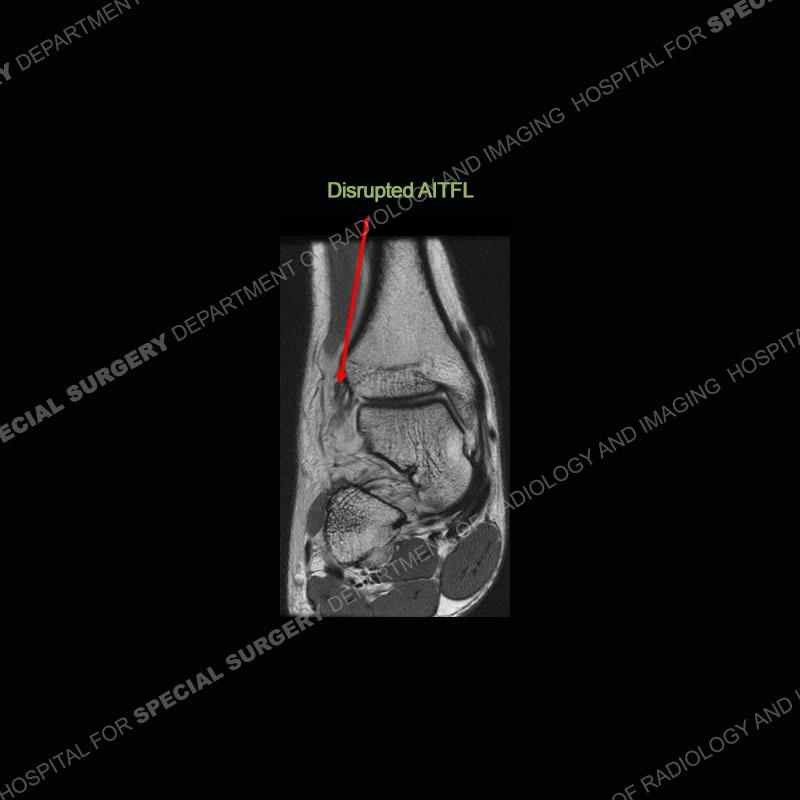

On the AP radiograph there is a diminished overlap of the distal tibia and fibula (normal is at least 10mm overlap). On the mortise view there is no overlap of the distal tibia and fibula and an increased distal tibial fibular clear space (normal is less than 5 mm and measured 1cm superior from the ankle joint). The MRI shows a disruption of the anterior inferior tibiofibular ligament (aitl), a disruption of the posterior inferior tibiofibular ligament (pitfl), and a disruption of the interosseous ligament. There is also a stripping of the distal interosseous ligament (IOL) from the tibia and a precipitated subperiosteal hematoma.

As compared to the more typical ankle sprain of the lateral collateral ligaments, this can be a much more significant injury requiring much greater time away from sport and necessitating surgical intervention. This case was just a nice example of classic findings on radiographs and MRI. The radiographs can be enhanced with external rotation stress views to demonstrate abnormal widening of the ankle joint. On MRI, the AITFL, PITFL, and IOL can all be especially well seen on axial images to evaluate the extent of injury. In this case, the transverse tibiofibular ligament (or deep portion of the PITFL) was maintained and not highlighted. The AITFL is the first ligament to be injured with subsequent injury to the remainder of the ligaments if greater force is imparted.